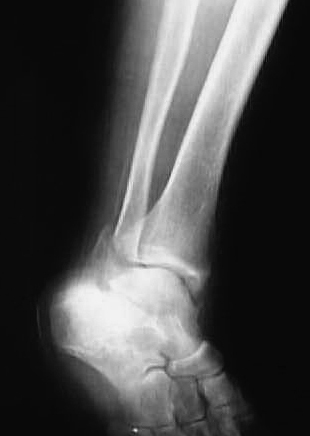

正面像において腓骨下端部の骨折が認められ、中枢骨片の内側への転位が認められた。側面像において中枢骨片は前下方、末梢骨片は外後上方の骨片への転位が認められた(図1、2)。

図1

図2